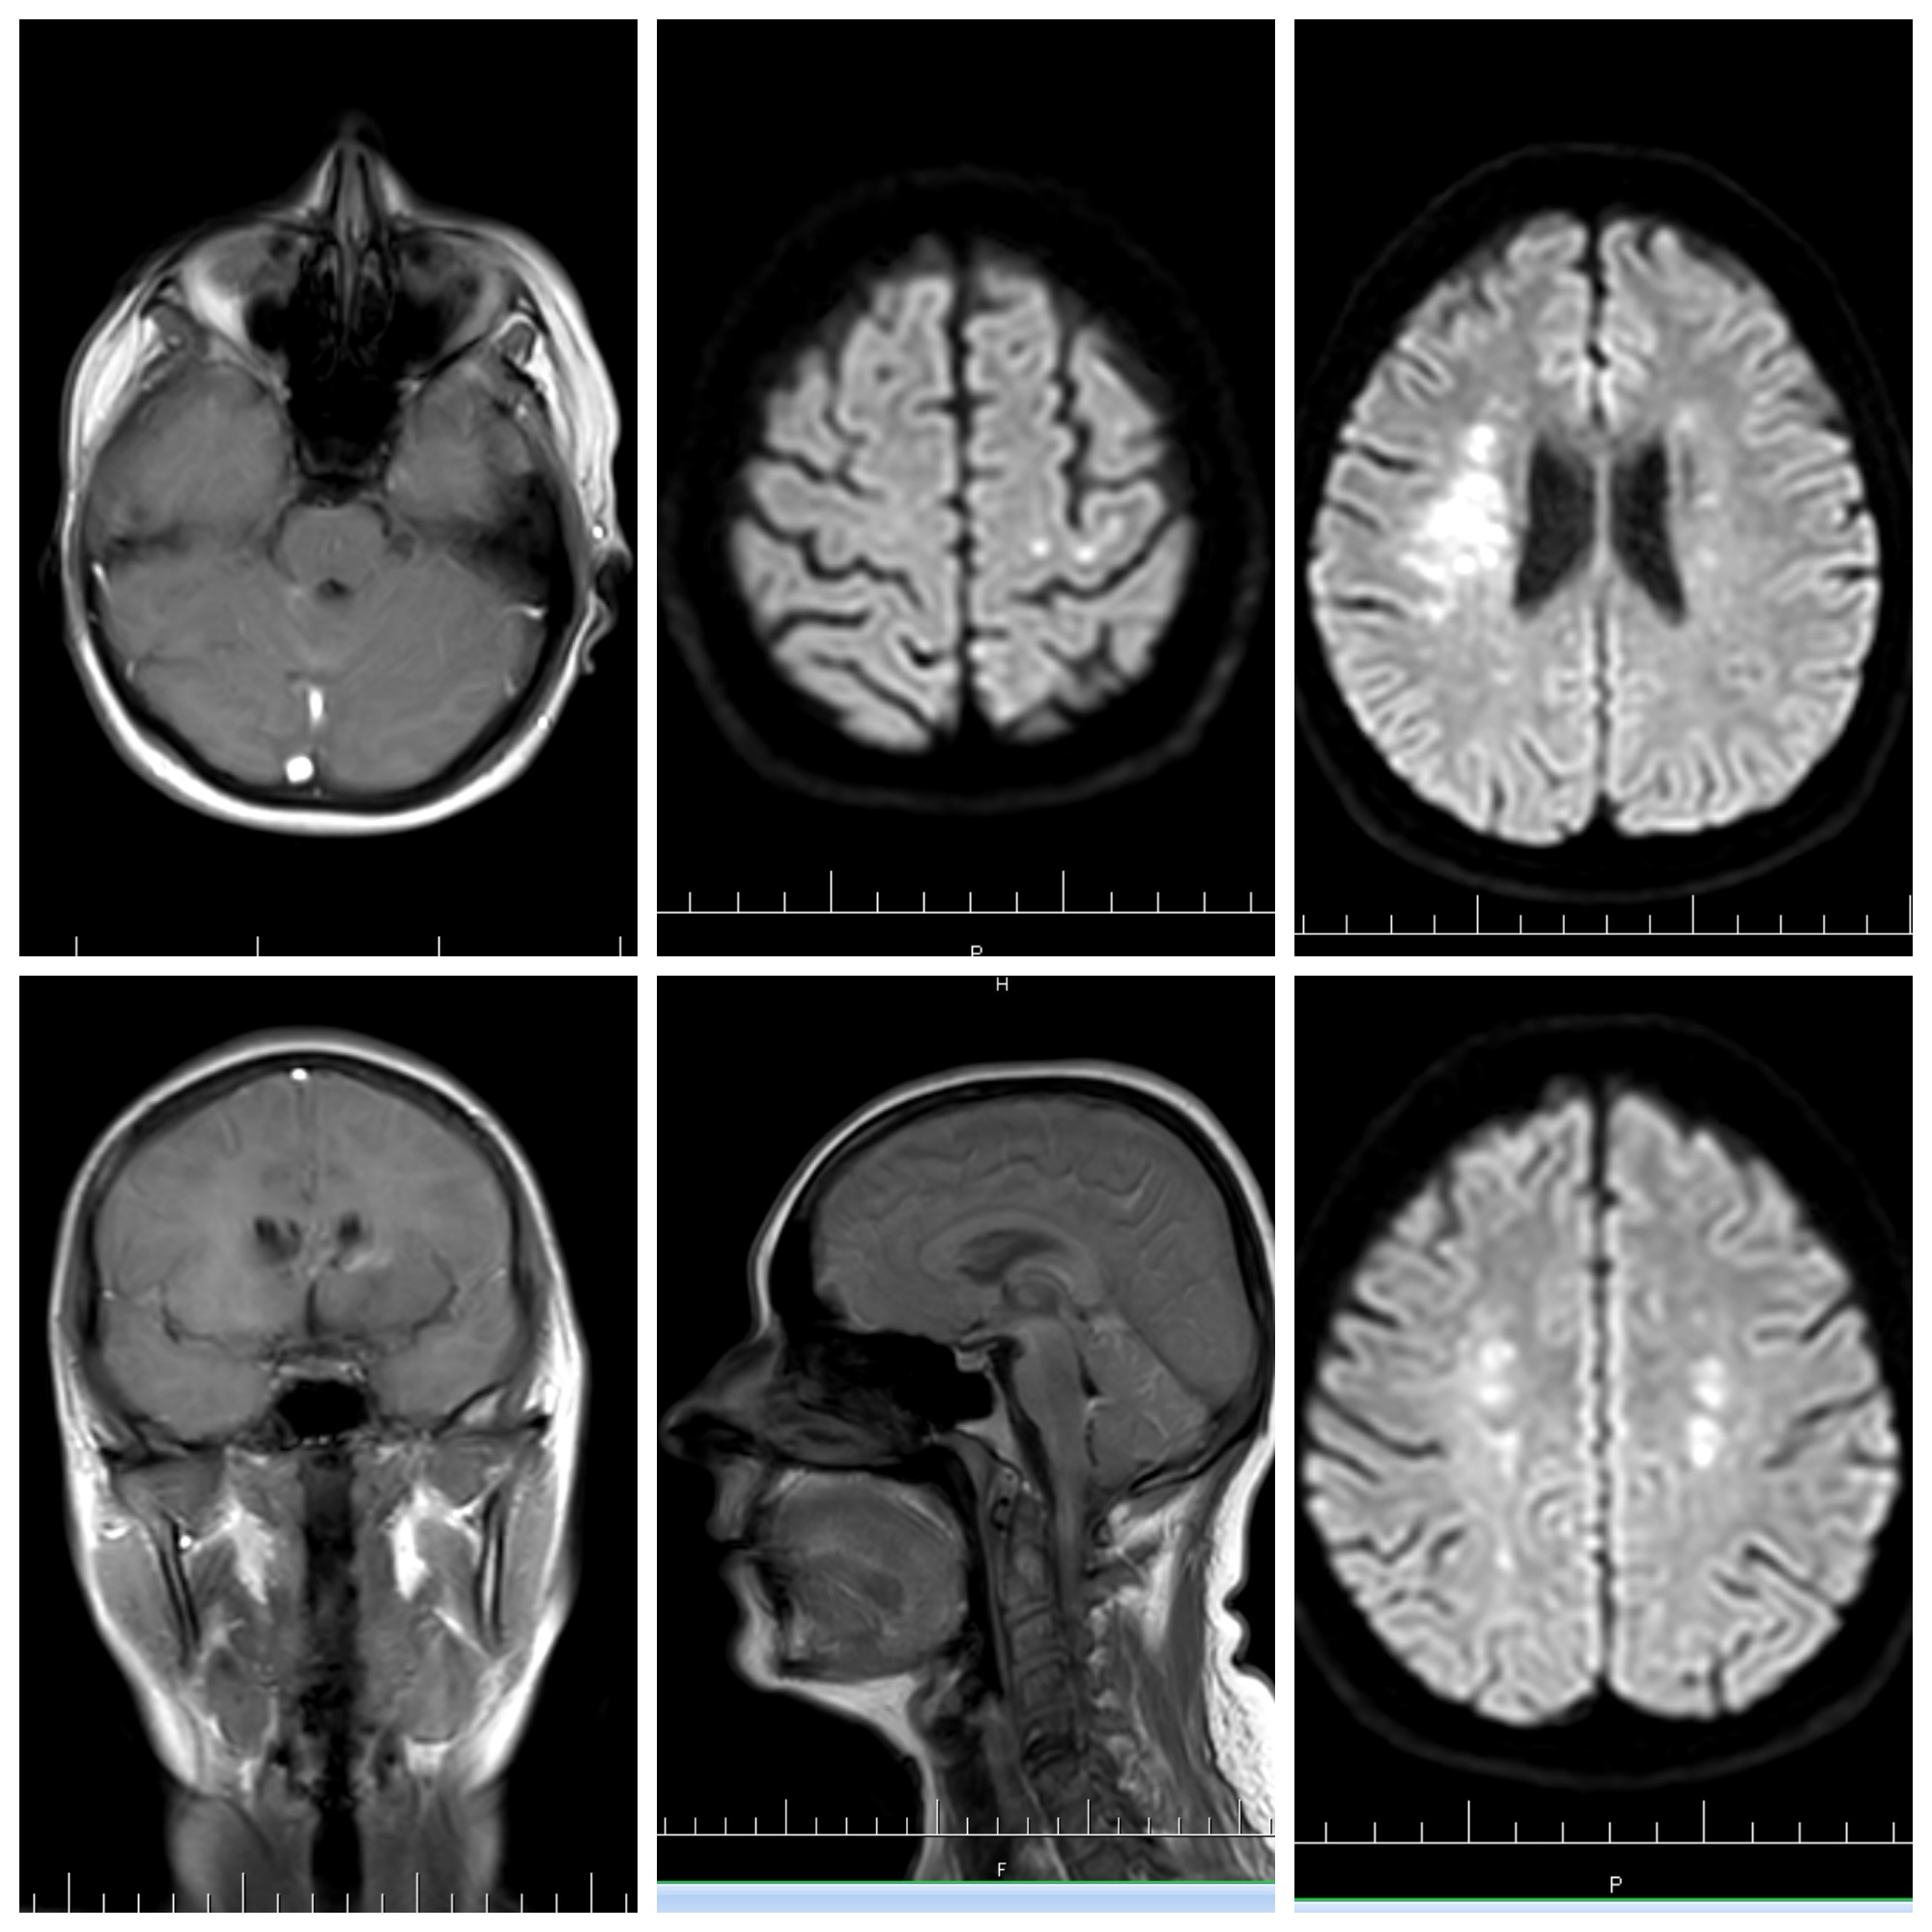

lézie na mozgu = skleróza multiplex

V mozgu su nejake biele miesta...